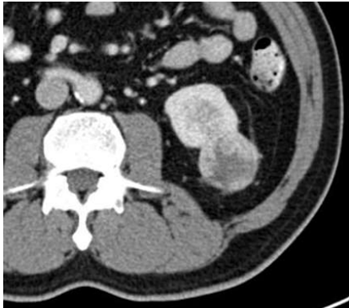

Sobre as imagens a seguir: assinale a alternativa

correspondente à classificação de Bosniak para cada

imagem.

I.

II.

III.

IV.